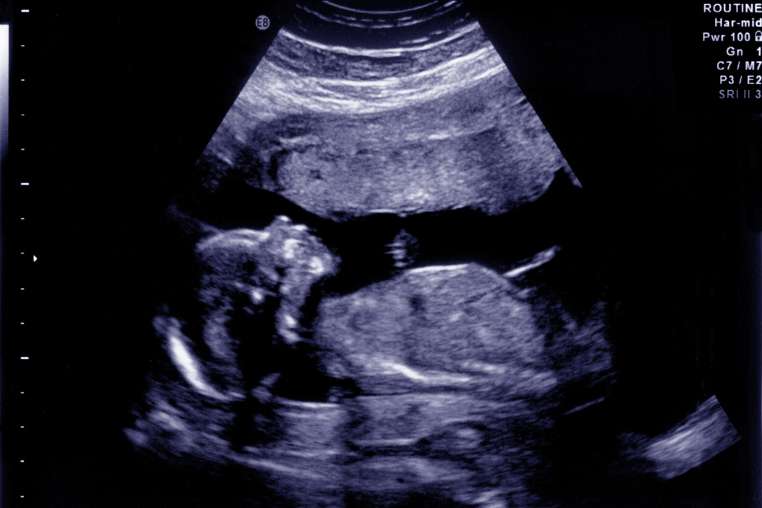

Về chẩn đoán, siêu âm hình thái học và siêu âm 3D/4D giúp phát hiện bất thường hình thể. Các xét nghiệm sàng lọc trước sinh như Double test, Triple test hay xét nghiệm NIPT cho phép đánh giá nguy cơ rối loạn nhiễm sắc thể. Khi cần thiết, bác sĩ có thể thực hiện chọc ối, sinh thiết gai nhau để phân tích di truyền, hoặc dùng MRI thai nhi để khảo sát các cơ quan phức tạp như não và tim.